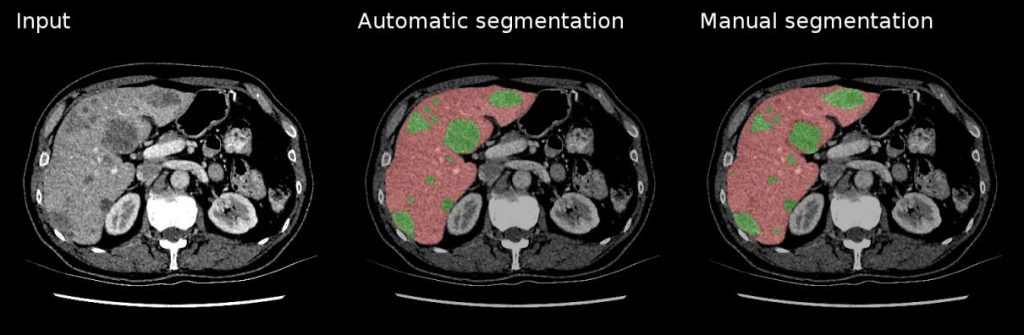

3. Image Segmentation and Annotation Segmentation is a crucial task in medical imaging for identifying and delineating structures of interest, such as organs or tumors. Generative AI can automate the segmentation process, saving time and reducing manual effort. Furthermore, it can generate annotations for training deep learning models, facilitating the development of accurate and efficient algorithms.